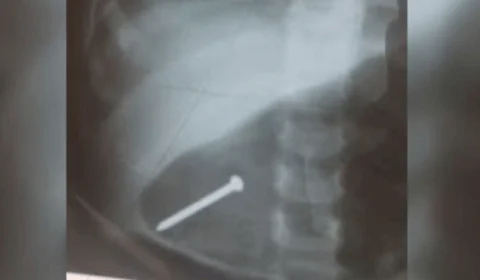

Bebê de 1 ano é internada após engolir prego enquanto brincava em casa

Bebê de 1 ano é internada após engolir acidentalmente prego durante brincadeira em casa no Pará.